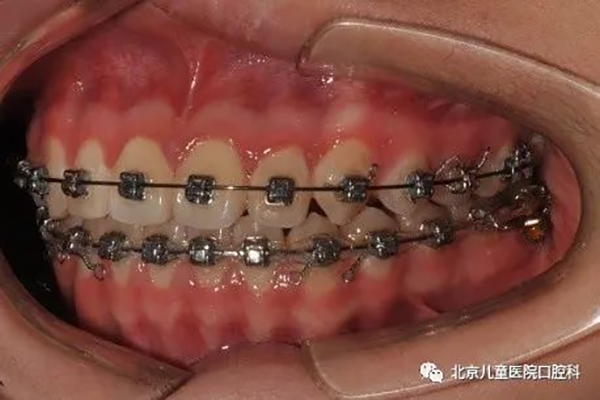

3、牙列整体远移,见于轻度牙列不齐,轻度牙齿前突,或轻度地包天的病例。

治疗中